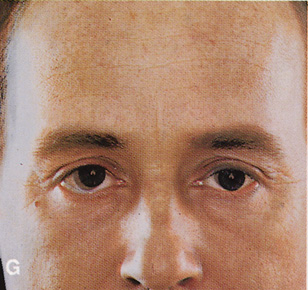

Fig. 6. Lateral orbitotomy through upper eyelid skin crease A. Photo demonstrating right globe ptosis present for more than 2 years. B. Axial CT scan showing a well outlined oval lesion in the lacrimal gland

fossa. C. Coronal CT showing lesion pushing globe inferiorly. D. Skin crease excision marked for lateral orbitotomy. E. Lateral orbital rim exposed. Bone cuts made above frontozygomatic suture

and at zygomatic arch. F. Lateral wall removed. Subperiosteal space exposed. Hard tumor could be

palpated in area of lacrimal gland. G. Benign mixed tumor of lacrimal gland removed. H. Bone sutured into place. I. Skin crease closed. |